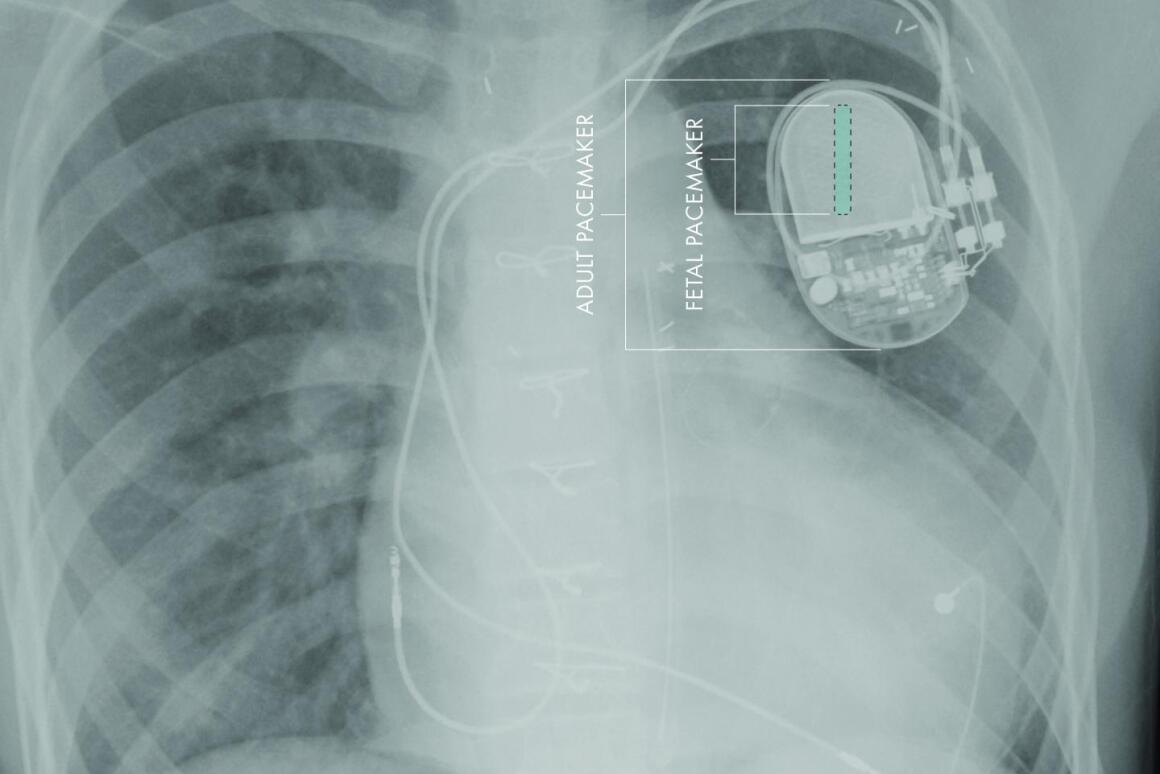

Miniature Pacemaker Designed To Be Implanted In Fetuses